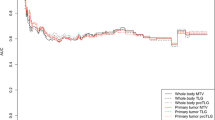

The median follow-up time was 19 months (range 6–43 months). The median OS time was 18 months (6–41 months). The median of EFS was 11.6 months (3–41 months). Figure 1 illustrates outcomes in patients at the time of the last follow-up.

Post-therapeutic indices

Follow-up PET parameters of the primary tumour were prognostic factors for EFS. The higher the SUVmax, SUVpeak, SUVmean, TV and TLG after induction chemotherapy, the shorter the EFS (p < 0.05). Figures 2 and 3 illustrate the effect of TVF and TLGF after induction chemotherapy on EFS. Patients with a TVF <22 ml or TLGF <66 ml after induction therapy had better EFS than those with higher values (p < 0.05). CTV after chemotherapy was also a prognostic factor for EFS, but CTD was not.

Index ratio

Changes in TV and TLG between the baseline and follow-up PET/CT scans were the only significant predictive indices for outcome. The higher the TVF or TLG ratio, the shorter the EFS (p < 0.05). Figure 4 illustrates the effect of TLG ratio on EFS. Patients with a TLG ratio < 0.48 after induction treatment had better EFS than those with a TLG ratio > 0.48 (13.9 vs. 9.2 months, p = 0.04). The other ratios, i.e. CTD, CTV, SUVmean, SUVpeak or SUVmax ratios, were not prognostic factors for EFS. SUVmax ratios on dominant mediastinal LN were not prognostic factor for EFS or OS.

A few recent studies have suggested a prognostic value of metabolic TV in lung cancer [26–29]. Recently, whole-body TLG before therapy has been found to be a prognostic factor in NSCLC [29]. Nonetheless, to the best of our knowledge, volume-based measurements have never been evaluated in the assessment of therapeutic response in NSCLC. Our data showed that only the decrease in metabolic volume-based measurements of the primary tumour after induction chemotherapy was associated with prognosis, in contrast to decreases in SUVmax, SUVmean or SUVpeak (Fig. 5). This concept of studying the changes in the whole tumour has already been observed with anatomical imaging. Zhao et al. showed that volumetric tumour measurement in CT scans was better than unidimensional tumour measurement at distinguishing tumour sensitive and resistant to gefitinib [30]. TV and TLG enable a global evaluation of tumour shrinkage under treatment and can capture changes in the whole tumour mass. SUVmax measurements alone may be misleading for heterogeneous lung tumours. After treatment, tumour response is also heterogeneous with death of susceptible tumour cells and proliferation of more virulent tumour cells. Moreover, the host inflammatory response under treatment can induce an increase in tumour metabolism [31–33]. All these drawbacks may be mitigated by metabolic volume-based evaluation with TV or TLG. Moreover, CTV changes under chemotherapy failed to predict significantly EFS in our study, emphasizing the strength of metabolic volume changes regarding prognosis.